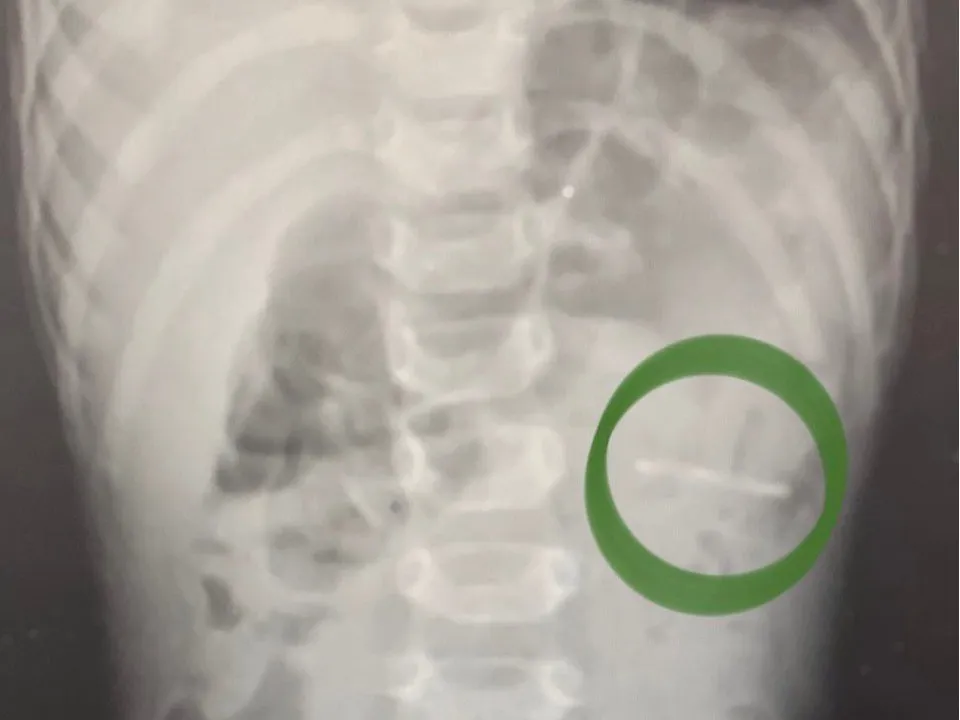

Годовалый ребенок нечаянно проглотил крупный ключ-открывашку от алюминиевой банки. Родители немедленно привезли мальчика в приемное отделение Раменской больницы. Ребенку выполнили рентген-исследование органов брюшной полости и смогли обнаружить расположение предмета — он был в желудке.

«Слизистые оболочки внутренних органов были не повреждены. При помощи эндоскопического инструмента металлический предмет с острыми краями был аккуратно извлечен. Очень важно, что при попадании в организм инородного тела лучше не пытаться вытащить его самостоятельно, а обратиться за медпомощью, не вызывать рвоту, не давать есть и пить до осмотра врача», — объяснил заведующий детским хирургическим отделением Раменской больницы Владимир Хабалов.